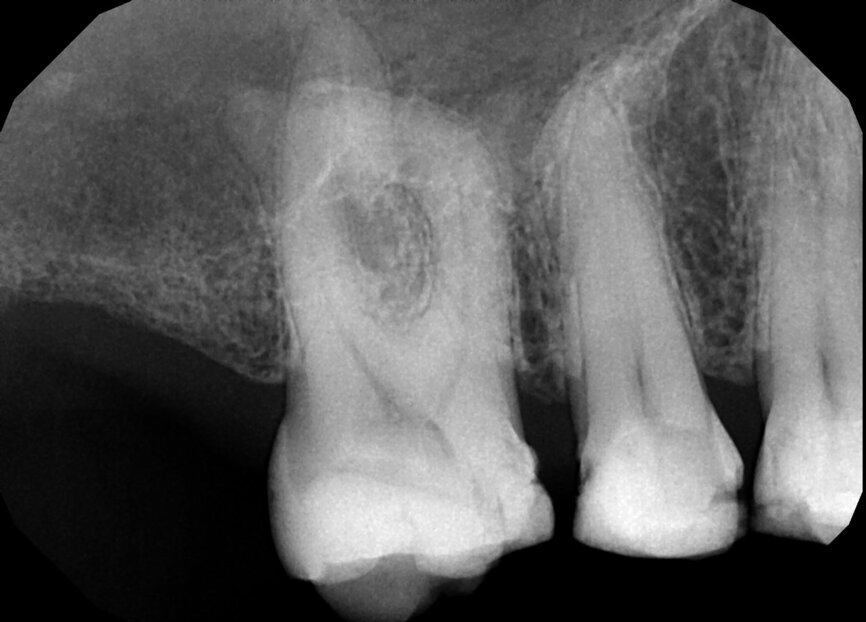

Fig. 17a: Case assisted with CBCT to determine anatomy pre-operatively. Note the multiple cross sections moving apically and the correlation to the 2-D view. Note also the conservative taper in relation to the root width. (Courtesy of Dr. Brett Gilbert)

Fig. 17b: Case assisted with CBCT to determine anatomy pre-operatively. Note the multiple cross sections moving apically and the correlation to the 2-D view. Note also the conservative taper in relation to the root width. (Courtesy of Dr. Brett Gilbert)

Fig. 17c: Case assisted with CBCT to determine anatomy pre-operatively. Note the multiple cross sections moving apically and the correlation to the 2-D view. Note also the conservative taper in relation to the root width. (Courtesy of Dr. Brett Gilbert)

Fig. 17d: Case assisted with CBCT to determine anatomy pre-operatively. Note the multiple cross sections moving apically and the correlation to the 2-D view. Note also the conservative taper in relation to the root width. (Courtesy of Dr. Brett Gilbert)

Fig. 17e: Case assisted with CBCT to determine anatomy pre-operatively. Note the multiple cross sections moving apically and the correlation to the 2-D view. Note also the conservative taper in relation to the root width. (Courtesy of Dr. Brett Gilbert)

Fig. 17f: Case assisted with CBCT to determine anatomy pre-operatively. Note the multiple cross sections moving apically and the correlation to the 2-D view. Note also the conservative taper in relation to the root width. (Courtesy of Dr. Brett Gilbert)

Managing complex anatomy is much simpler if the clinician has a pre-operative road map. The CBCT provides the roadmap and the surgical microscope the lens (literally) through which to visualize the result. Aside from a relaxed patient who is profoundly numb, being able to visualize anatomy by taking a pre-operative (and possibly intra-operative) CBCT and using a surgical microscope during treatment have no substitutes. They are the current “Gold Standard” in that 3-D imaging shows the clinician the true reality of a clinical situation as opposed to the suggestion gained from a 2-D radiograph. Proper interpretation of imaging prior to and/or during endodontic treatment goes a long way in taking the “guesswork” out of identifying canal location and other anatomical complexities as the procedure unfolds. In a 2014 study by El Fayad and Johnson, it was determined that when having a pre-operative CBCT as compared to 2-D radiographs alone, the treatment plan was modified 62 percent of the time. This is a huge game changer to think that the information learned from 3-D imaging changed the plan of treatment over six times out of 10 (Fig. 4).[2]